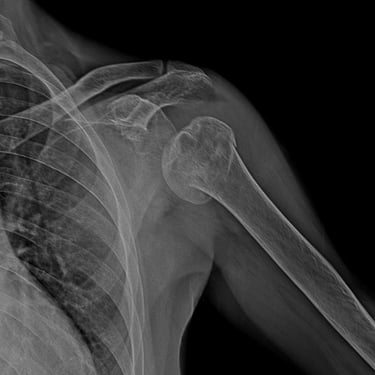

Shoulder arthroscopy and rotator cuff repair

Trauma (Fractures)

Orthopedic trauma (fractures) refers to injuries to the musculoskeletal system, like bones, joints, and muscles, often from accidents, falls, or sports